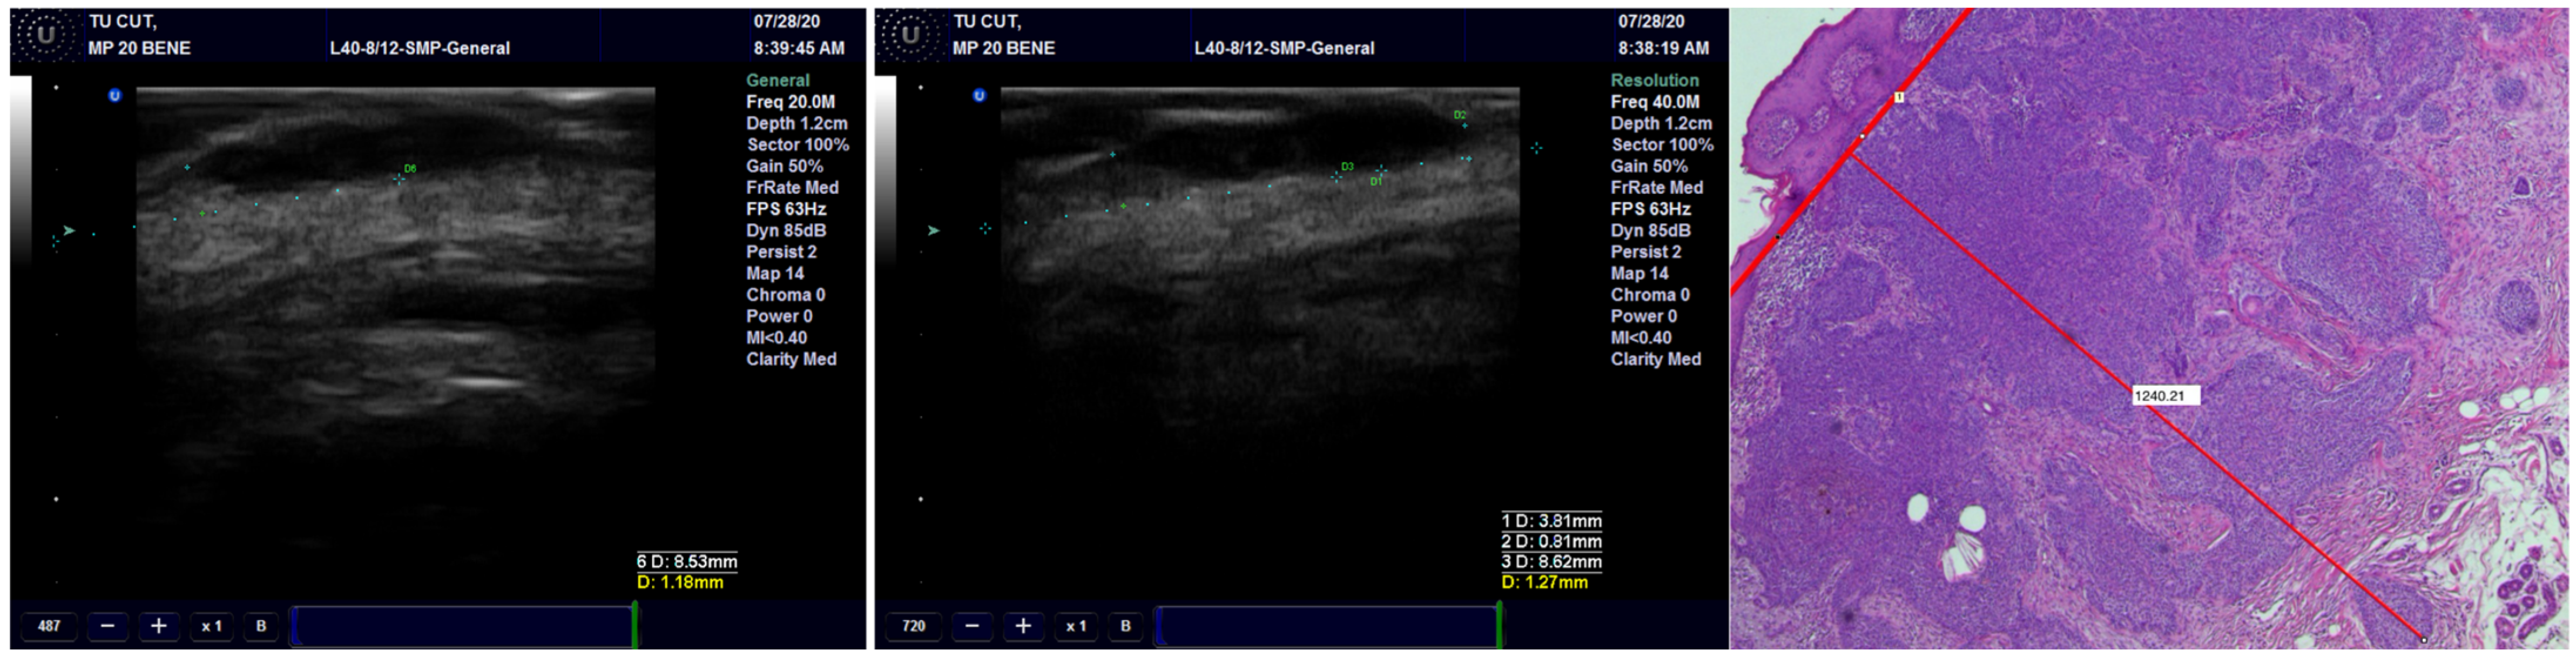

Concerning concordance between the histopathological and echographic measurements of tumor thickness, we found excellent agreement for all transducers, with the best ones being for the preoperative observations and the least favorable ones being the postoperative observations (Figure 3) (Table 2). Within any of the preoperative and postoperative observations, the 40 MHz transducer fared the best, followed by the 20 MHz transducer and finally by the 13 MHz transducer.

Figure 3.

The thickness of the tumor, measured on US with 20 MHz and 40 MHz transducers, compared with the pathological image of the tumor showing very high occurrence of US.

We assessed the concordance between the final diagnosis and ultrasound diagnosis, and we found a Cohen’s Kappa of 0.8897 (95% CI: 0.6783–1.1011), bias-adjusted Kappa of 0.8895 and prevalence- and bias-adjusted Kappa of 0.9355 (Table 3). The concordance between the final diagnosis of BCC and the presence of hyperechoic spots followed an identical pattern. We have associated the presence of the hyperechoic spots with diagnosis of BCC (Figure 4). Only one case of BCC was misdiagnosed by echography due to the missing hyperechoic spots (Figure 5).

Figure 4.

The arrow is showing the presence of the hyperechoic spots in a BCC and the pathological correspondence.